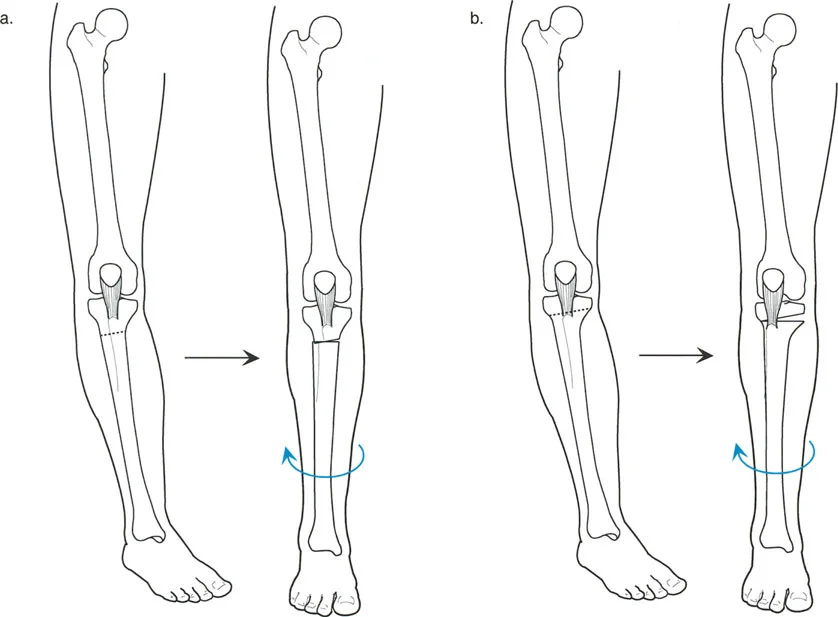

ب. قطع العظم الفاروسي (Varus Osteotomy)

- متى يستخدم: يُطبق في حالات فحج الورك (Coxa Valga)، حيث تكون الزاوية بين عنق وجسم الفخذ كبيرة جدًا، أو في حالات التهاب المفاصل التنكسي (الخشونة) لتحويل مناطق تحمل الوزن في المفصل، أو عندما يكون رأس الفخذ بيضاوي الشكل.

- الهدف: تقليل الزاوية بين عنق وجسم الفخذ، مما يزيد من ذراع الرافعة للعضلات المبعدة ويقلل الضغط على المفصل. قد يؤدي هذا إلى إزاحة المدور الكبير للأعلى، مما يستدعي إجراء نقل للمدور الكبير لتعويض هذا التأثير.

- التقنيات:

- قطع عظم نيشيو (Nishio Osteotomy): طورها نيشيو عام 1984. تتضمن قطعًا دائريًا (Dome Osteotomy) يقع وسطيًا للمدورين الكبير والصغير. يتم وضع مركز هذا القطع الدائري في مركز عنق الفخذ. يؤدي هذا إلى إزاحة المدور الكبير للأسفل والجانب، مما يعوض تأثير التقصير لقطع العظم الفاروسي ويحافظ على ذراع الرافعة للعضلات المبعدة أو يزيدها.

صورة توضيحية لقطع عظم نيشيو الدائري الذي يهدف إلى تقليل إزاحة المدور الكبير للأعلى.